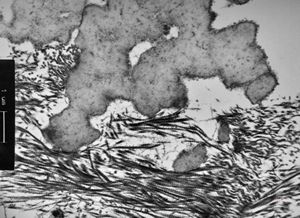

M,7y. | epidermolysis bullosa (dystrophic type) - oral mucosa